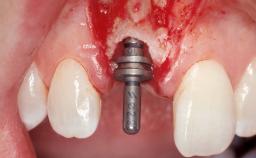

Late Placement of an Implant in a Maxillary Left Central Incisor Site

Type of Implants Two-Piece

Bone Augmentation Horizontal|Staged

Augmentation Materials Xenogenous|Membrane

Soft Tissue Grafting Simultaneous

Bone Volume Deficient horizontally, requiring prior grafting